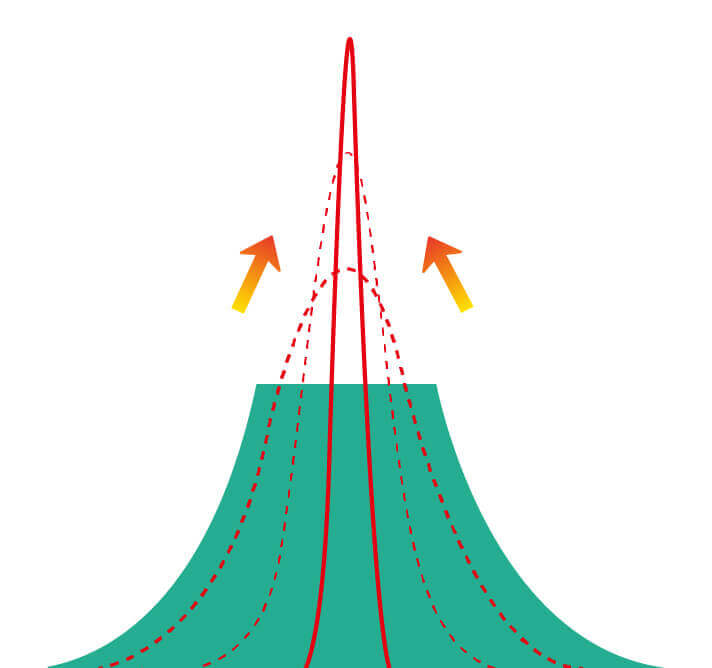

(Spectral Focused lmaging, SFI)

能够凸显黏膜浅层和中层血管轮廓,适用于中、远景观察下的病灶识别和早癌筛查。

照明光谱

照明光谱

光谱提取

光谱提取

光谱提取能量汇聚

光谱提取能量汇聚

RGB图像重建

RGB图像重建

染色模式显示

染色模式显示